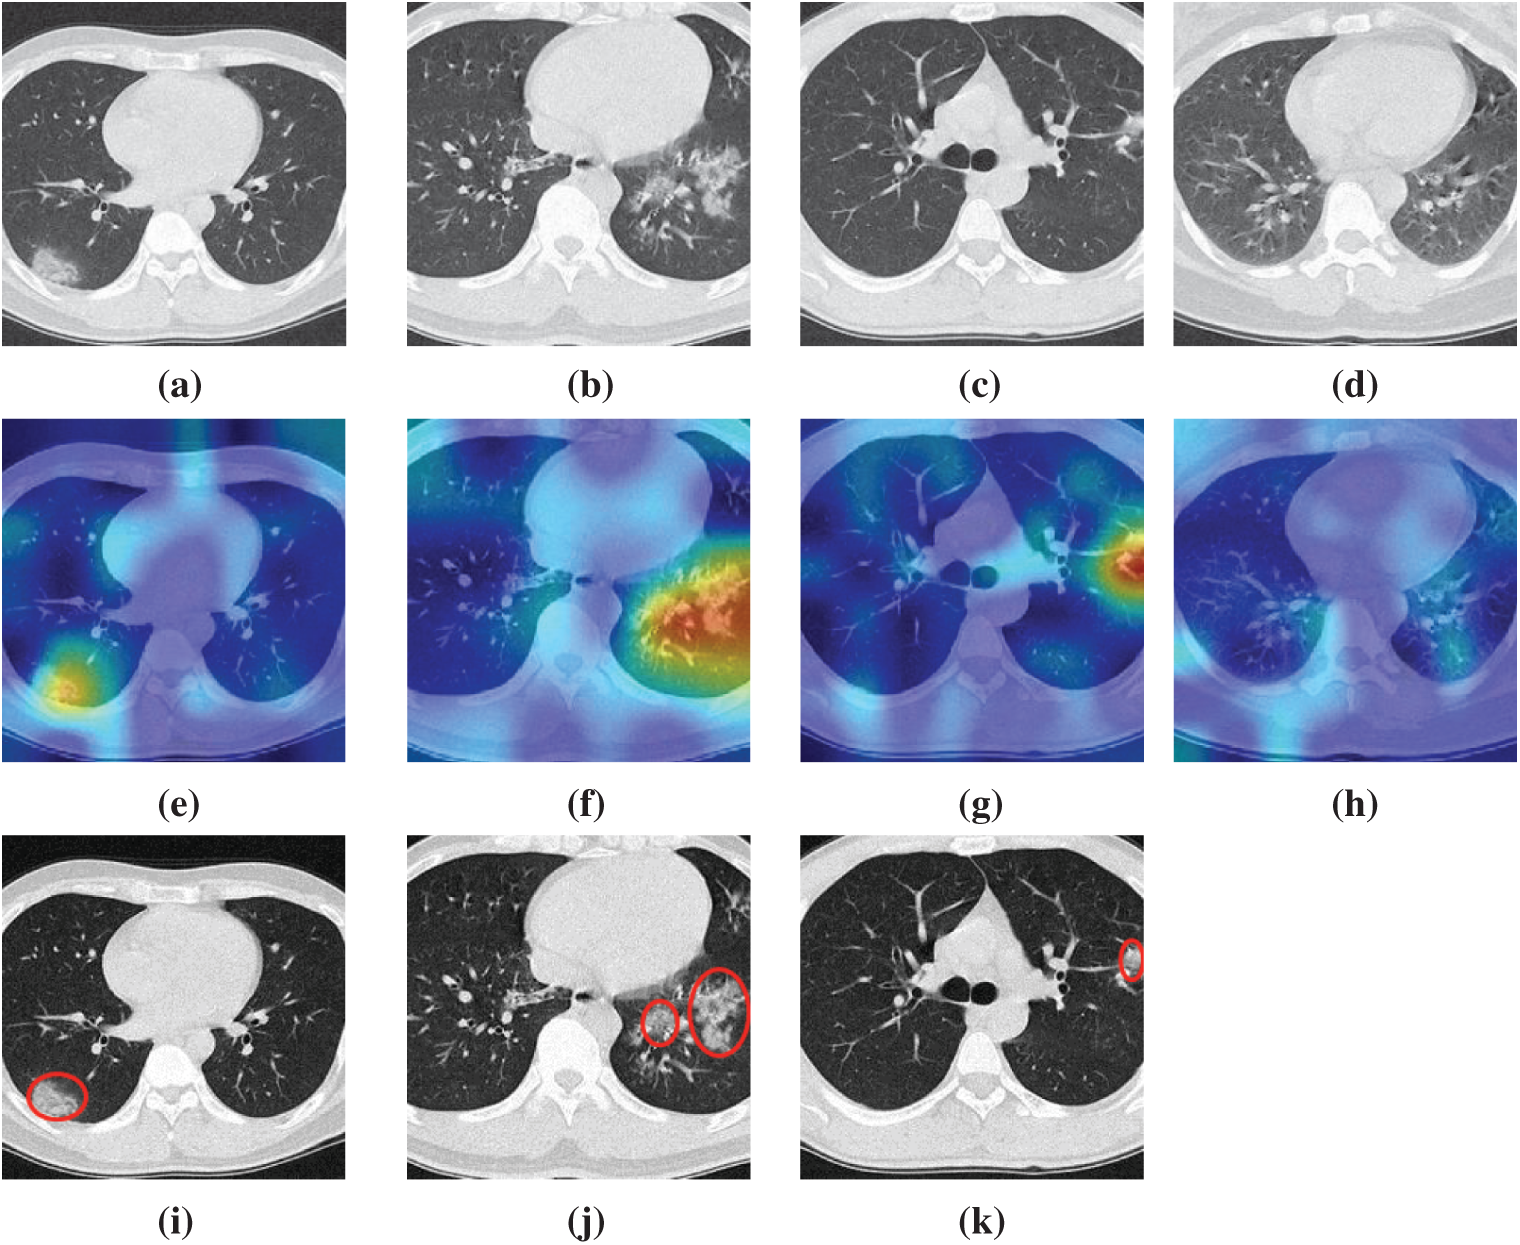

We take four samples (one sample per category) as examples, the raw images of those four pictures are shown in Figs. 7a–7d, their corresponding heatmaps are shown in Figs. 7e–7h, and the cognate manual delineation results are shown in Figs. 7i–7k. It is noteworthy there are no lesions within healthy subject images.

Figure 7: Heatmaps of three diseased samples and one healthy sample (a) A sample of COVID-19 (b) A sample of CAP (c) A sample of SPT (d) A sample of HC (e) Heatmap of COVID-19 (f) Heatmap of CAP (g) Heatmap of SPT (h) Heatmap of HC (i) Lesion of (a) (j) Lesion of (b) (k) Lesion of (c)

The FM of NRAPM-5 in DRAPNet is used to generate the heat maps by Grad-CAM. We can see from Fig. 7 that the heatmaps by this DRAPNet model and Grad-CAM are able to apprehend the diseased lesions efficiently and to ignore those non-lesion areas. Conventionally, AI is viewed as a “black box”, which hurdles its widespread use. Nevertheless, with the help of explainability of modern AI techniques, the radiologist and patients could gain assurances to this DRAPNet model, since the heat map gives a self-explanatory interpretation of how AI classifies COVID-19, CAP, SPT from healthy subjects.